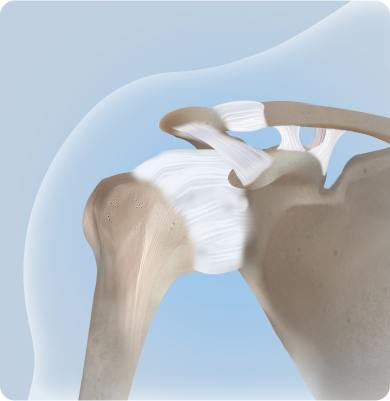

어깨 관절을 감싸고 있는 회전근개 힘줄이 손상되거나 찢어지는 질환

회전근개파열 어깨 관절을 감싸고 있는 회전근개 힘줄이 손상되거나 찢어지는 질환

어깨를 움직일 때 어깨뼈와 힘줄이 충돌하여 염증과 통증을 유발하는 질환

팔을 반복적으로 머리 위로 들어 올리는 동작이나 잘못된 자세, 외상, 나이로 인한 퇴행성 변화 등이 원인이 됩니다.